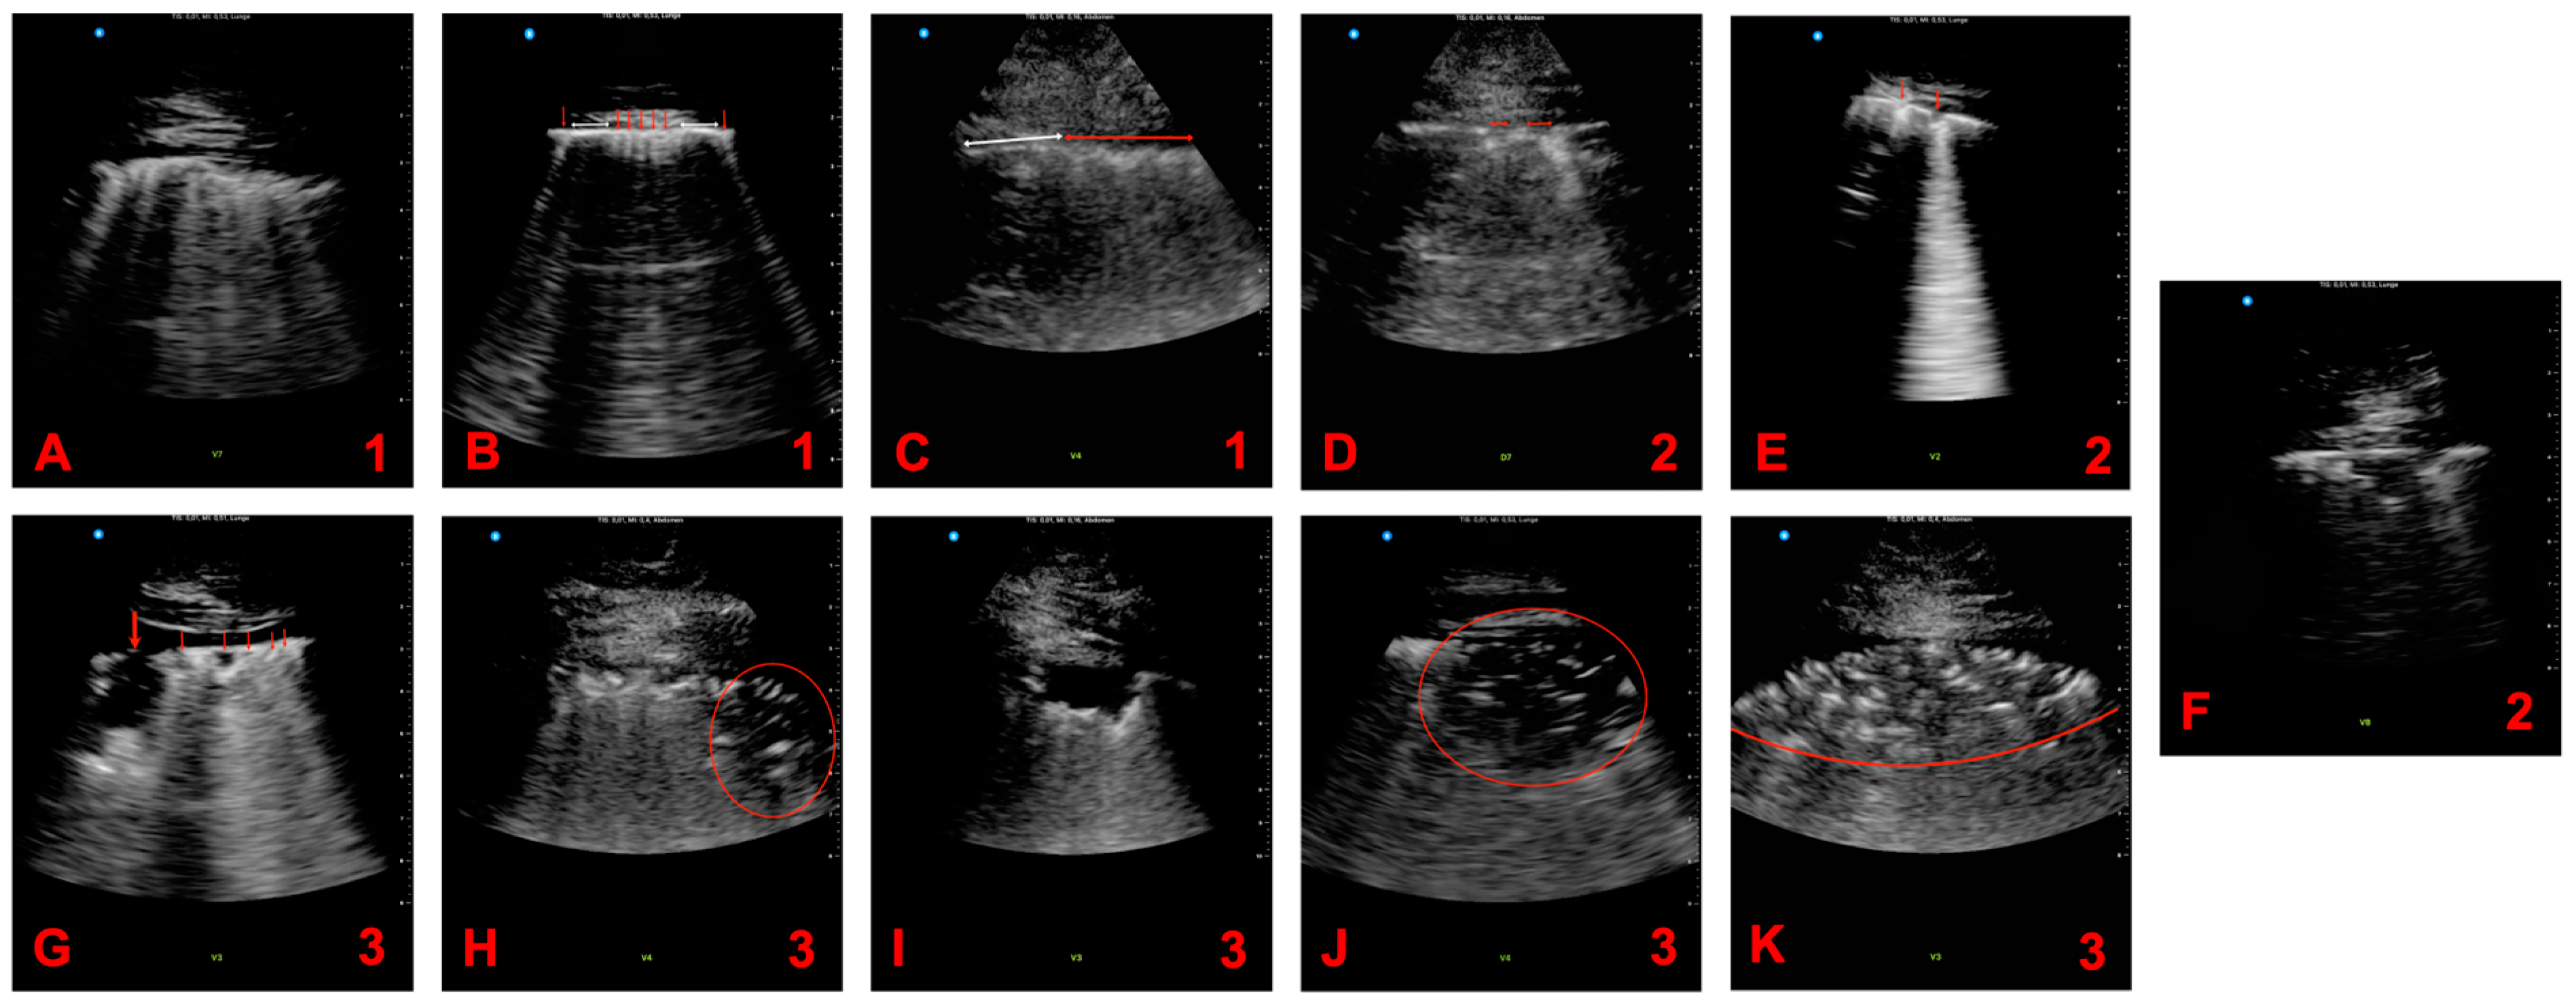

2.1. Ultrasound Examination

2.2. Scoring System

3.2. Pathologies in Lung Ultrasound